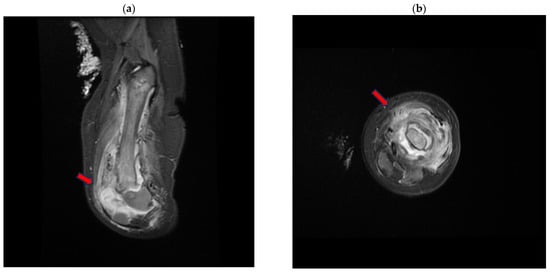

| M/1.33 | 2019 | HEP A/RL. (HAVRIX); INFLUENZA/LL (FLULAVAL QUADRIVALENT); (MMR II)/LL; VARICELLA/RL (VARIVAX) | 1 | Pain when bearing weight on the right leg and difficulty walking, fever. Myositis, osteomyelitis, and a soft-tissue abscess in the right thigh | T2 hyperintense and diffusion restriction in the muscles, indicating myositis, and the femur, indicating osteomyelitis. A rim-enhancing fluid collection identified as a soft-tissue abscess (MRI) | NR | Unspecified AB | NR |